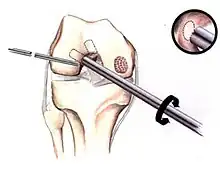

Arthroscopic image of OATS surgery on the medial femoral condyle of the knee

Intact lesions

If non-surgical measures are unsuccessful, drilling may be considered to stimulate healing of the subchondral bone. Arthroscopic drilling may be performed by using an antegrade (from the front) approach from the joint space through the articular cartilage, or by using a retrograde (from behind) approach through the bone outside of the joint to avoid penetration of the articular cartilage. This has proven successful with positive results at one-year follow-up with antegrade drilling in nine out of eleven teenagers with the juvenile form of OCD,[53] and in 18 of 20 skeletally immature people (follow-up of five years) who had failed prior conservative programs.[54]